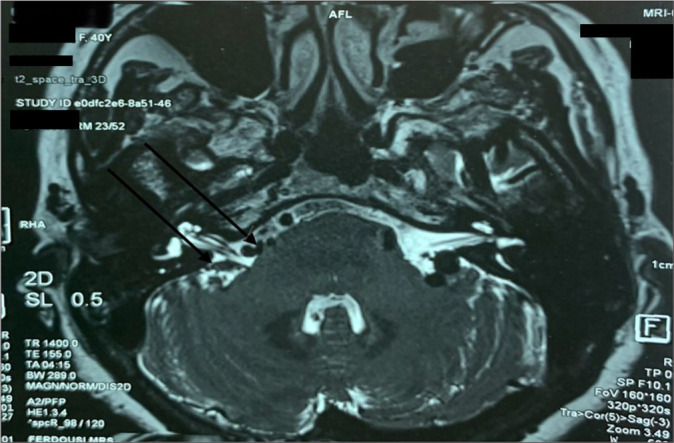

Case description: We report a case of a 40-year-old female suffering from debilitating right-sided facial pain due to a rare "scissor effect" produced by the superior petrosal sinus and Dandy's vein (vein of the cerebellomesencephalic fissure) compressing the trigeminal nerve. Surgical decompression was performed by interposing autologous skeletal muscle wrapped with Surgicel between the conflicting venous structures and the nerve. The patient achieved complete pain relief without neurological deficits.